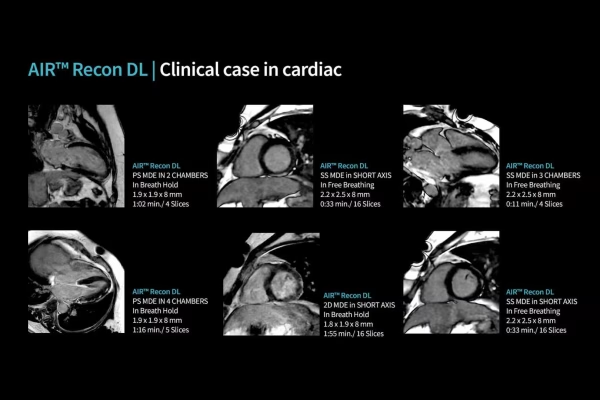

IRM GE Signa Explorer 1.5T